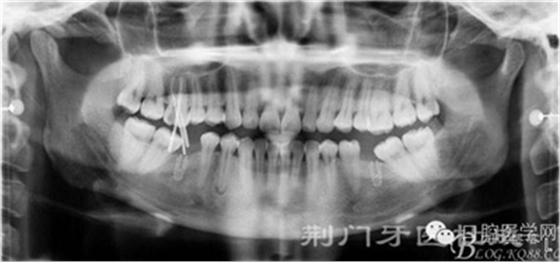

病人資料:汪XX 女 29歲 主訴: 右上后牙疼痛3天余

現(xiàn)病史:右上后牙疼痛3天余,多年前在其他的地方拔過雙側(cè)下頜后牙,來院就診。 既往史: 治療史,(無重大疾病,身體良好)。

檢查:16齲壞穿髓,探(-)叩(+++),無松動,36 46 缺失,37 47 近中傾斜嚴重,44畸形中央尖牙體變色,叩(+),溫度測試無反應 ,18 28 38 48 萌出牙體偏頰

診斷:

1:16 根尖炎

2:44根尖炎

3:牙列缺損

4:18 28 38 48 異位萌出

X線片